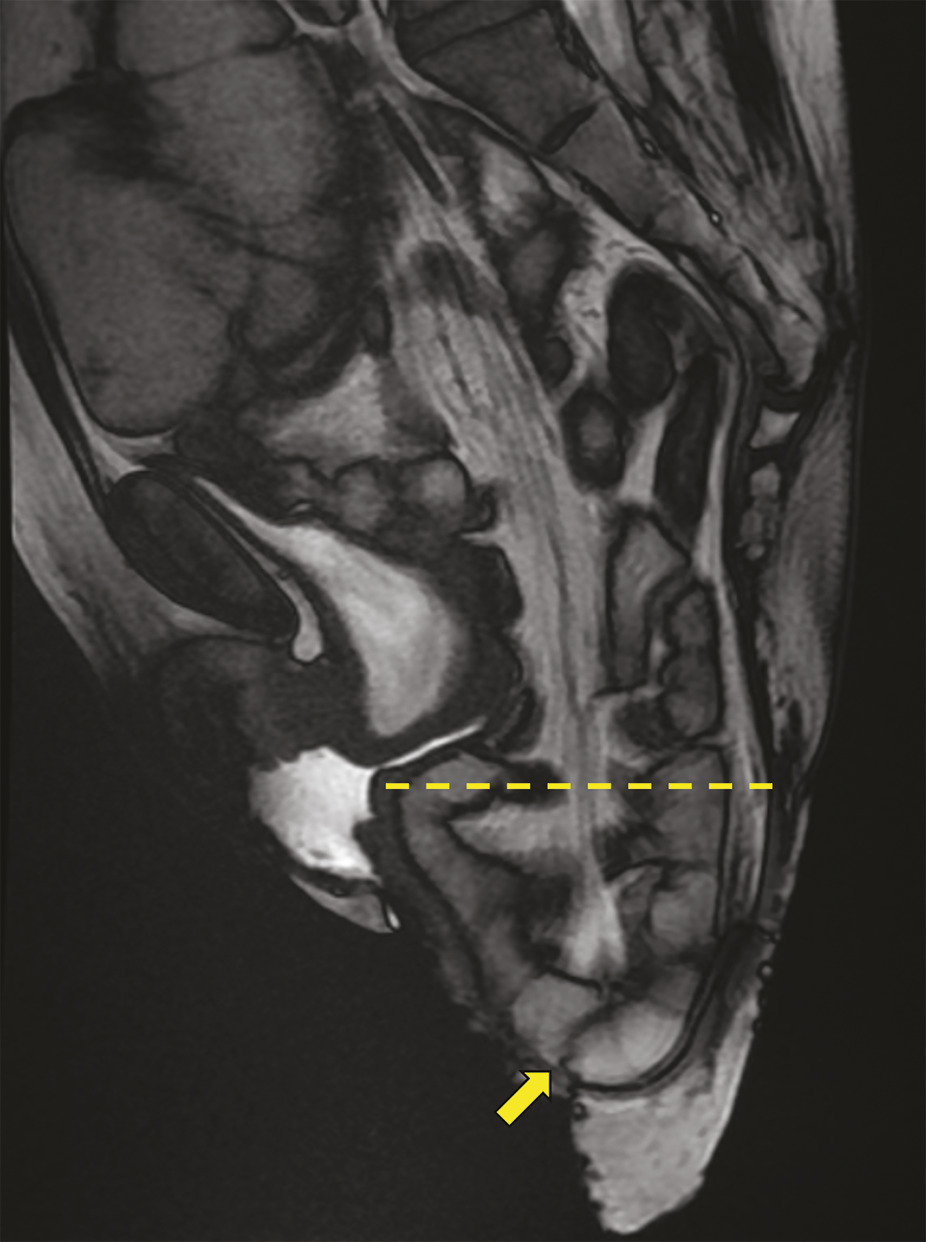

IRM. Séquence dynamique en poussée maximale montrant un volumineux prolapsus rectal externe associé à une entérocèle (descente des anses grêles) trans-recto-anale (flèche).